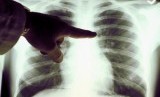

REPUBLIKA.CO.ID, JAKARTA – Ketua Umum Yayasan Kanker Indonesia Prof DR dr Aru Wisaksono Sudoyo, Sp.PD-KHOM, FINASIM, FACP mengatakan, gejala pada kanker paru kerap tidak nampak ketika penyakit berada di stadium awal. Akibatnya, data saat ini menunjukkan bahwa 60 persen pasien kanker paru datang dalam stadium lanjut.

ru menjelaskan kanker paru memiliki gejala yang serupa dengan penyakit umum lainnya seperti TBC. Karena itu, penting bagi masyarakat untuk meningkatkan pengetahuan tentang faktor risiko, gejala, dan perawatan yang tersedia termasuk modalitas diagnosis kanker paru sehingga kanker paru dapat diobati dengan tepat.

Kanker paru dibedakan untuk setiap pasien dari jenis sel dan perubahan sel abnormal. Pengujian biomarker akan menunjukkan mutasi spesifik pada sel Kanker.

Pengujian biomarker penting karena dapat mendeteksi adanya penanda bilogis (biomarker) spesifik yang dapat membantu pemilihan terapi yang telah tersedia di Indonesia. Berdasarkan data Globocan 2020, di Indonesia terlihat dua masalah kanker paru, yaitu jumlah kasus paru yang terus meningkat dan hanya dapat diatasi dengan melakukan pencegahan atau pengendalian faktor risiko kanker paru.